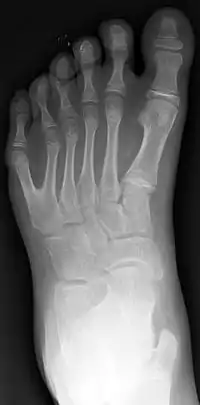

La polidactilia (del griego poly, ‘muchos’ y daktylos, ‘dedo’) es un trastorno genético donde un humano nace con más dedos en la mano o en el pie de los que le corresponde (normalmente un dedo más). Se detecta en el momento del nacimiento. A estos dedos se les llama «dedos extra» o «dedos supernumerarios».

El dedo adicional es generalmente un pequeño pedazo de tejido fino y suave. A veces contiene el hueso sin articulaciones; ocasionalmente el dedo se encuentra completo y funcional. El dedo extra suele ubicarse tras el meñique de la mano o del pie, es menos frecuentemente del lado del pulgar e inusualmente intercalado entre otros dedos. Suele ser una bifurcación de un dedo normal, y rara vez nace de la muñeca como los demás dedos.